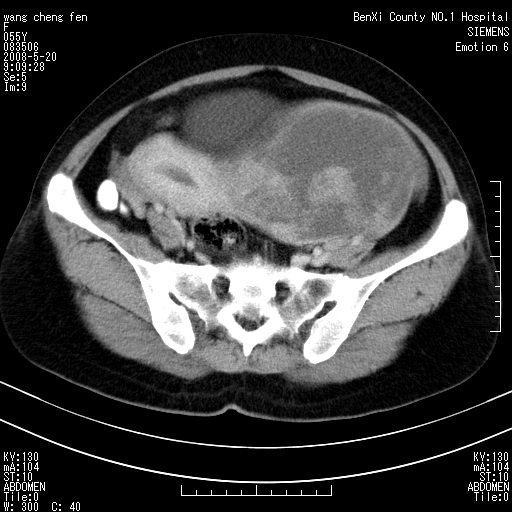

女、绝经后阴道流血3个月

左侧附件区巨大囊实性病灶,边缘光整,病灶囊壁较厚,增强示囊壁及实性部分明显强化,强化呈度与宫体实质大致相同,宫腔积液征像,未见盆腔积液等其他异常,考虑左侧卵巢囊腺癌,不除外囊腺瘤及浆膜下肌瘤坏死

左侧附件区巨大囊实性病灶,边缘光整,病灶囊壁较厚,增强示囊壁及实性部分明显强化,强化呈度与宫体实质大致相同,宫腔积液征像,未见盆腔积液等其他异常。绝经后阴道流血3个月,结合病史左侧卵巢囊腺癌首先考虑,宫腔扩大不除外累及。期待结果。

支持浆膜下子宫肌瘤.之前由于网络原因未看全图片,现在重看,宫颈见一类圆形低密度影,增强轻度强化,低于肌层强化,宫腔扩大,考虑宫颈癌伴宫腔积液可能性大.

1,宫颈部占位,宫颈癌?2,左侧附件区囊实性占位,界较清,实质部分强化明显。考虑浆膜下或阔韧带肌瘤囊变可能大。囊腺类肿瘤不除外。